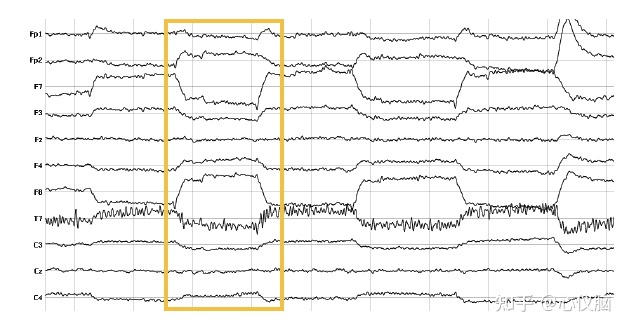

1.2眼动(HEOG)

与眨眼一样也是眼睛固有电压梯度的结果,眼睛运动时,头皮电压梯度会变得眼睛运动指向的方位更正。